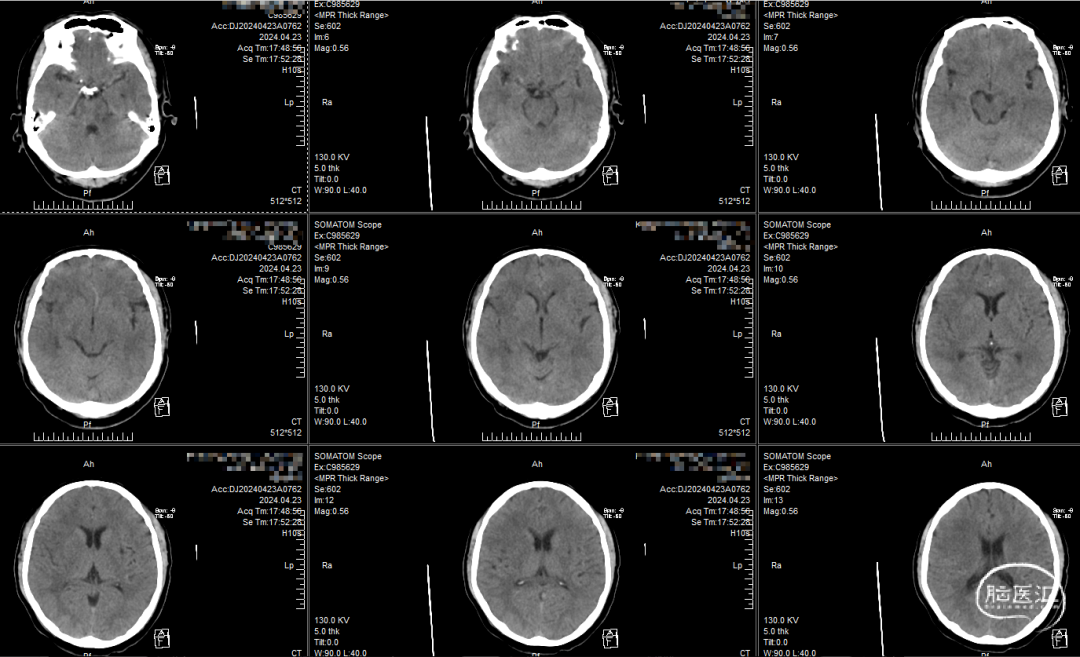

患者发病前mRS 0分;入院NIHSS 15分,ASPECT 7分

CT平扫:岛叶,大脑中动脉前皮质区受累,考虑大脑中动脉起始部闭塞可能性大

造影显示右侧大脑中动脉起始部闭塞

查体:NIHSS 15分,ASPECT 7分

病情较重,大脑中动脉闭塞诊断明确,静脉溶栓未能实现血管再灌注,侧支循环不能完全代偿大脑中动脉远端供血